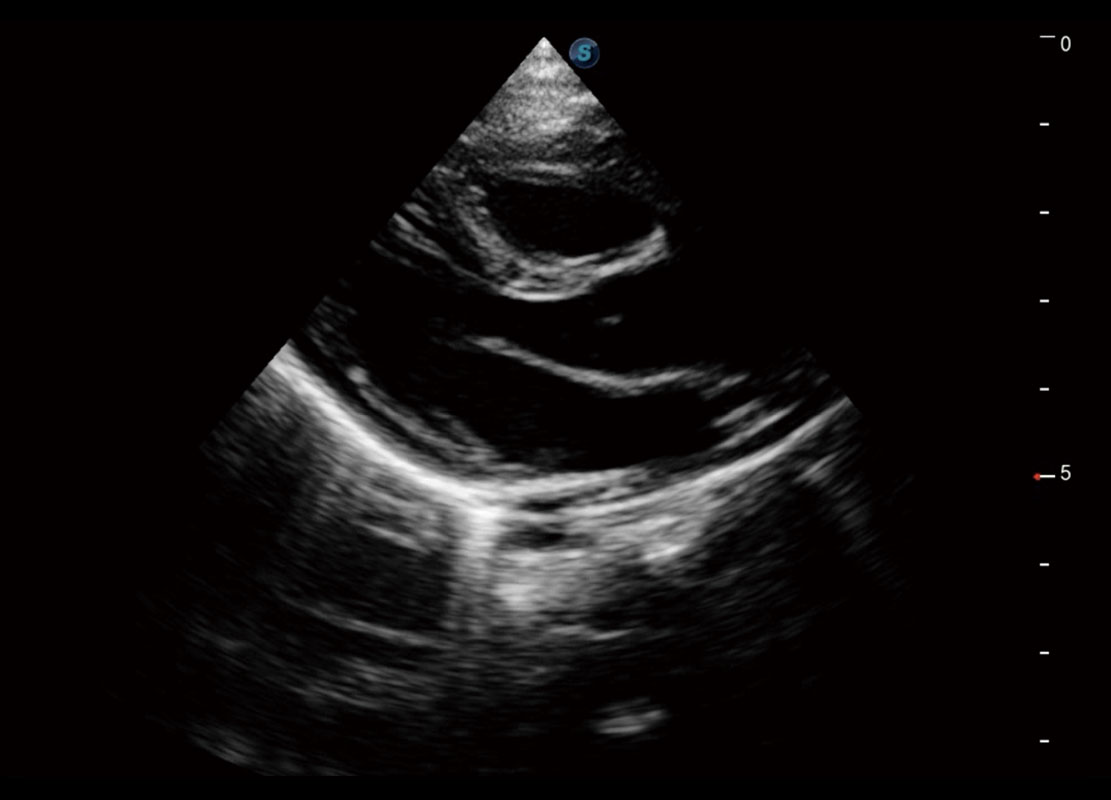

P60提供简单易学易用的高端诊断工具,为您中晚孕筛查提供快速清晰的解剖信息。

S-Fetus能够助您在实时扫查过程中自动识别标准切面、自动测量并录入报告。一个按键,即可快速、高效地获取胎儿生理指标,简化您的产科检查操作。